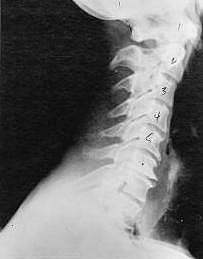

Near Normal

Subluxation Degeneration - Normal This is a side x-ray view of the neck. As with all the pictures you will see on this page, the patient is looking to the right of the screen, so you are viewing the right side of their neck. We will call this picture a "near normal" spine. Compare this spine with the ones you will see below on this page. Notice the normal forward curve of the neck. This curve helps absorb shock. Notice how each of the disc spaces between C2 (second bone in neck) and C7 are thick and even, this again is normal. Also notice how the front portions (right on the x-ray) of each of the vertebrae (called the 'body' of the vertebrae) are fairly square with clear and well defined borders. This type of arrangement is normal in the neck. Normal vertebrae in other parts of the spine also have similar characteristics to what we see here. When subluxations occur and are left uncorrected, ongoing relentless changes occur that result in damage to the structure and function of the spine along with nerve damage and the resulting problems caused from improper nerve supply.